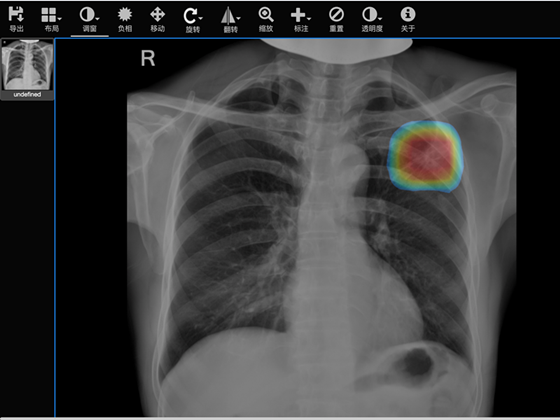

3月12日,由北京胸科医院医学影像科牵头的“评价肺结核影像筛查和辅助诊断软件安全性和有效性的多中心临床试验”项目正式启动。项目采用人工阅片对比人工智能AI阅片的方式,检验AI阅片的准确率以及软件稳定性。此举,北京胸科医院将“化身考官”助力人工智能影像AI驶入快车道。

3月12日,由我院医学影像科牵头的“评价肺结核影像筛查和辅助诊断软件安全性和有效性的多中心临床试验”项目正式启动,北京胸科医院专家“化身考官”,开启了对江西中科九峰智慧医疗科技有限公司开发的肺结核影像筛查和辅助诊断软件进行安全性和有效性考核。项目将人工智能影像阅读软件引入北京胸科医院,采用医生与人工智能阅读相同影像的方式,通过长时间的对比,对软件的准确率和稳定性进行审核,从而加速人工智能影像软件在医疗工作中的布局与应用。

北京胸科医院医学影像科侯代伦教授作为项目PI介绍到,在肺结核病的筛查过程中,胸部 DR或 CR扫描图像的诊断依赖于专业知识和医生的状态,在基层医院和边远地区医院中误诊漏诊难以避免。因此,寻找减少医生的阅片时间、增加工作效率和提高肺结核检出的敏感度与正确率,辅助临床诊断的方法,对于及早发现肺结核患者及正确指导肺结核患者的治疗有着重要的临床意义。

他说,随着计算机技术的不断进步,人工智能也随之飞速发展,尤其是在新冠疫情期间,人工智能大大提高了传染病影像诊断的效率,同时减轻医师的压力。项目成型后,人工智能影像AI将帮助医生减少阅片时间、增加工作效率,提高结核病的影像诊断能力,特别是将提升基层医院和边远地区医院肺结核检出的准确率,为今后胸部DR或CR的诊断开辟新道路,让医生阅片有更多的选择。